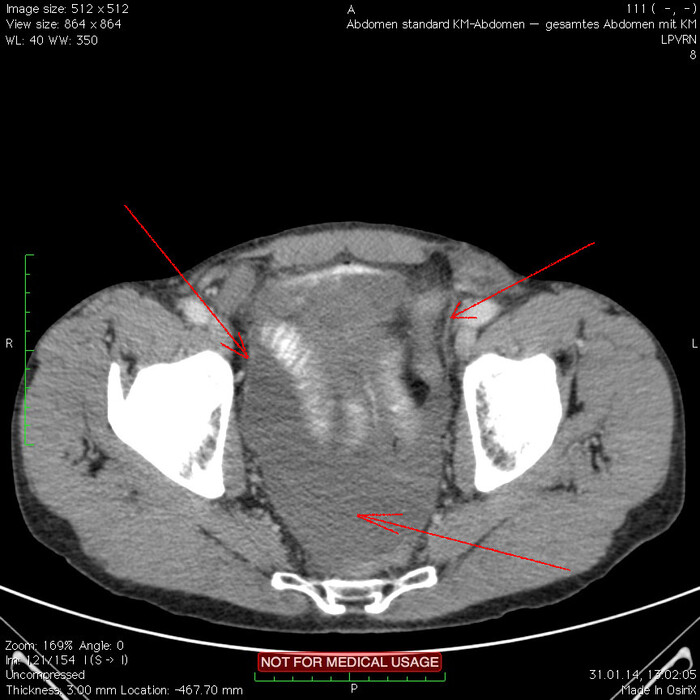

Мужчина, 32 года. Во время игры в футбол получил удар в низ живота, игру продолжил. Впоследствии боли в животе усиливались, стали нестерпимыми, ухудшилось общее самочувствие. На следующий день после игры пошёл сдаваться в больницу. Хирурги клинически описывают разлитой перитонит (воспаление брюшины) и отсылают пациента к нам на КТ, которое мы провели с внутривенной дачей контраста + заставили контраст ещё выпить (специальный раствор для перорального применения).

Так как клиника у нас острого живота после тупой травмы, учитывая что боли во всём животе и признаков большой кровопотери нет, то первое, что ищем - это свободный газ в брюшной полости, и находим его! (для этого лучше всего подходит т.н. лёгочное окно, как представлено ниже, или можно искать в костном окне - это спец.настройки яркости и контраста для просмотра разных структур тела - лёгкие, мозг, мягкие ткани, кости):

Отмечаем про себя, что в верхних квадрантах свободного газа не так уж и много. При перфорации желудка газа намного больше. Также выясняем, что газ есть также и в нижних квадрантах:

Ещё бросается в глаза массивный выпот (стрелки) во всех этажах, а также утолщение брюшины на всём протяжении, что указывает на диффузный (разлитой) перитонит. Тут, кстати, уже мягкотканное окно:

Итак, имеет место быть свободный газ в брюшной полости + свободная жидкость + перитонит. Определённо перфорация! Осталось найти источник. Желудок не подходит по механизму, а точнее по локализации травмы. Мочевой пузырь - в нём нет воздуха. Остаётся методом исключения только кишечник. Толстый или тонкий? Явно не верхние отделы толстого кишечника (ободочная кишка в области печеночного и селезеночного углов, а также поперечная исключаются - было бы больше воздуха). Сигма и нисходящая тоже заполнены стулом и воздухом. Получается, что тонкий кишечник всему виной.

Верхние (проксимальные) отделы точно не причём. Жидкость (звёздочки) больше в малом тазу, тут же и воздух. Для сравнения верхний этаж:

Hижний этаж:

И тут СТОП! А это чтo такое???

Кишке это точно не принадлежит, как ни крути. Это вышедший за пределы кишки контраст, который пациент выпил!

Осталось только место выхода найти:

Итого: перфорация тощей кишки в дистальных отделах, разлитой перитонит.

Был успешно прооперирован, место перфорации ушито, выписан.